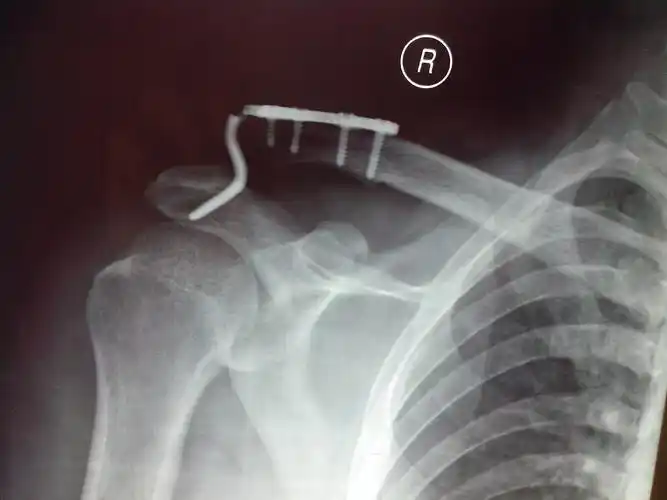

锁骨钩钢板的固定术后5月钩断裂